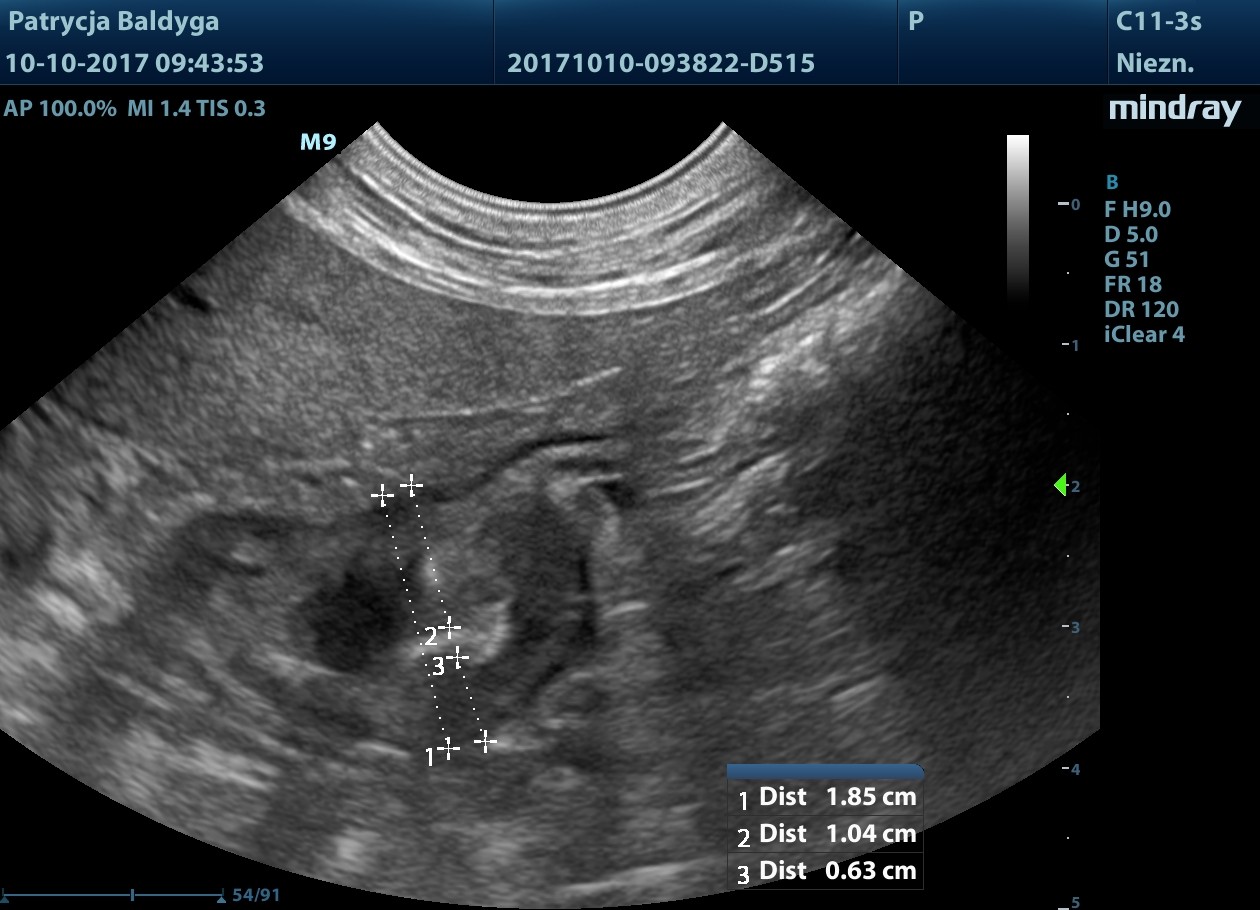

w końcowym odc. okręznicy poprzecznej nadśledzionowo widoczna zmiana ogniskowa

naciekowa, śródścienna, hipoechogenna, niesymetryczna 6-18 mm, dł. 2,5 cm, warstwowość w tym miejscu zatarta, obecny okoliczny, nieznaczny odczyn zapalny (pod koniec filmu 3), ww, chłonne okrężnicze środkowe reaktywne, powiększone, hipoechogenne, zokrąglone, śr. ok. 7-8 mm